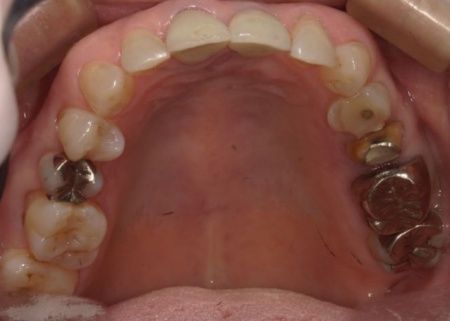

70代女性 歯根が折れた左上奥歯を抜いてインプラント治療で噛み合わせを回復した症例

拝見したところ、左上奥歯2本(第1小臼歯、第2小臼歯)の被せ物が外れていたため、レントゲン撮影で詳しく検査をした結果、歯根が折れていることが確認できました。

また、以前歯の神経を除去する根管治療を受けたそうですが、その際に使用された細い器具 (リーマー)の破片が根管内に残っています。

さらに、歯の周囲にある歯周ポケットの深さを測定したところ、口蓋側(上顎の内側)は歯根の先端まで達していました。

これでは、再度根管治療を行っても歯茎の状態が改善する可能性は低いと考えられます。

このまま放置すると周囲の骨や歯茎に炎症が広がるリスクがあるため、早急に適切な治療をする必要があると診断しました。